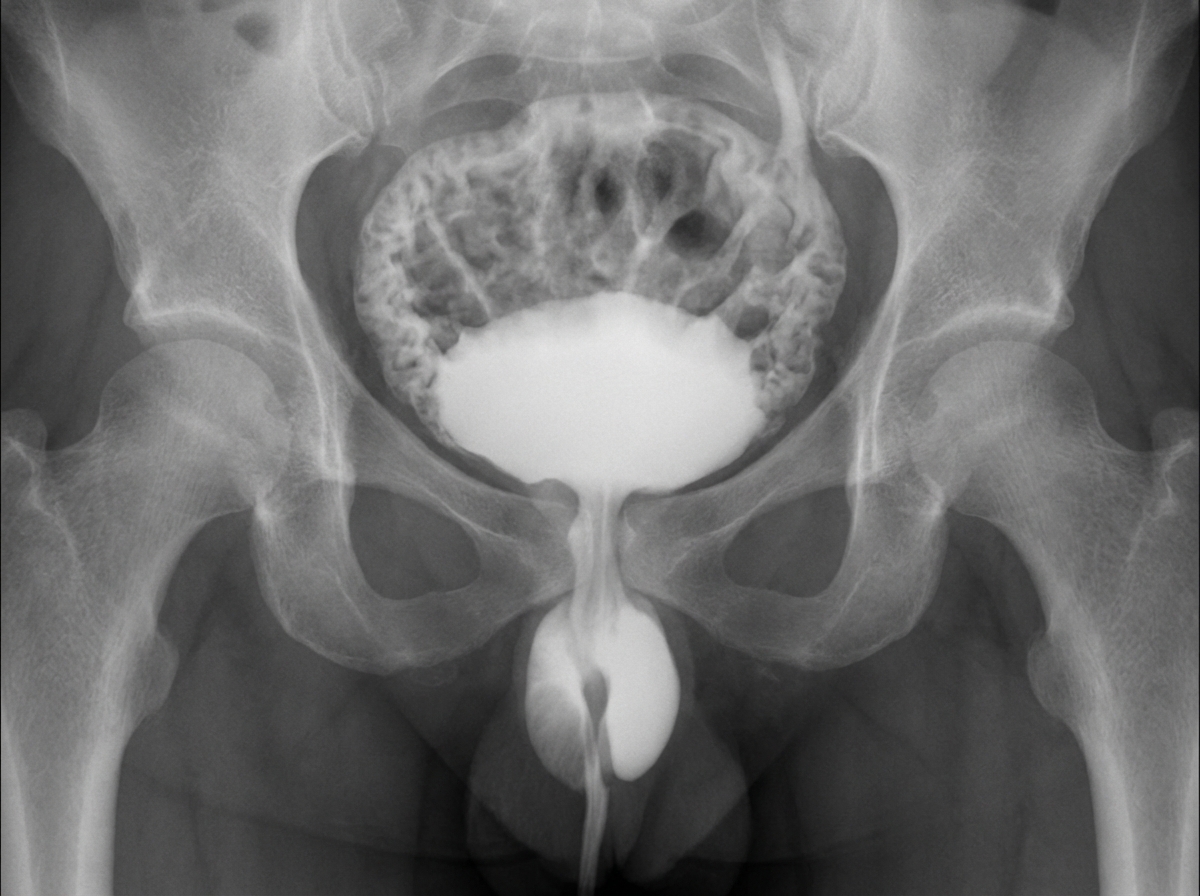

A male child presents with repeated urinary infections and failure to gain weight. A MCU was carried out as shown in the provided image. What is the most probable diagnosis?

Explanation: ***Posterior urethral valve*** - **Male child** with **recurrent UTIs** and **failure to thrive** along with characteristic **MCU findings** showing **dilated posterior urethra** and **trabeculated bladder** strongly suggests posterior urethral valve. - **PUV** causes **bladder outlet obstruction** leading to **vesicoureteral reflux**, **hydronephrosis**, and the classic **keyhole sign** on imaging studies. *Meatal stenosis* - Typically presents with **narrow urinary stream** and **dysuria** but does not cause the severe **bladder trabeculation** and **upper tract dilatation** seen on MCU. - Would show **narrowing at the urethral meatus** rather than **posterior urethral dilatation** characteristic of this case. *Bladder diverticulum* - Presents as **outpouching of bladder wall** on imaging and may cause **urinary stasis** but is uncommon in children. - Does not typically cause the **posterior urethral dilatation** and **keyhole appearance** seen in posterior urethral valves. *Bladder polyp* - Usually presents as **filling defects** within the bladder on imaging rather than **urethral dilatation**. - **Benign bladder masses** are rare in children and do not cause the characteristic **obstructive uropathy** pattern seen in this case.